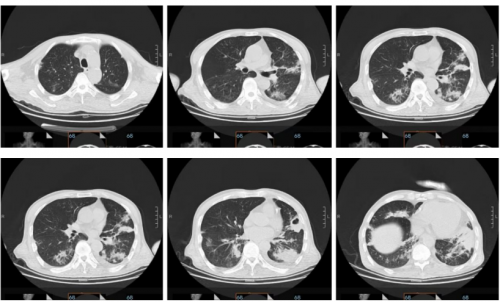

10.15日胸部CT:肺内多发炎症,支气管炎。双肺上叶局限性气肿。双侧胸膜增厚。纵隔稍大淋巴结。

10月26日复查肺ct略有吸收,局部形成空腔。少量胸腔积液。

10.26肺ct